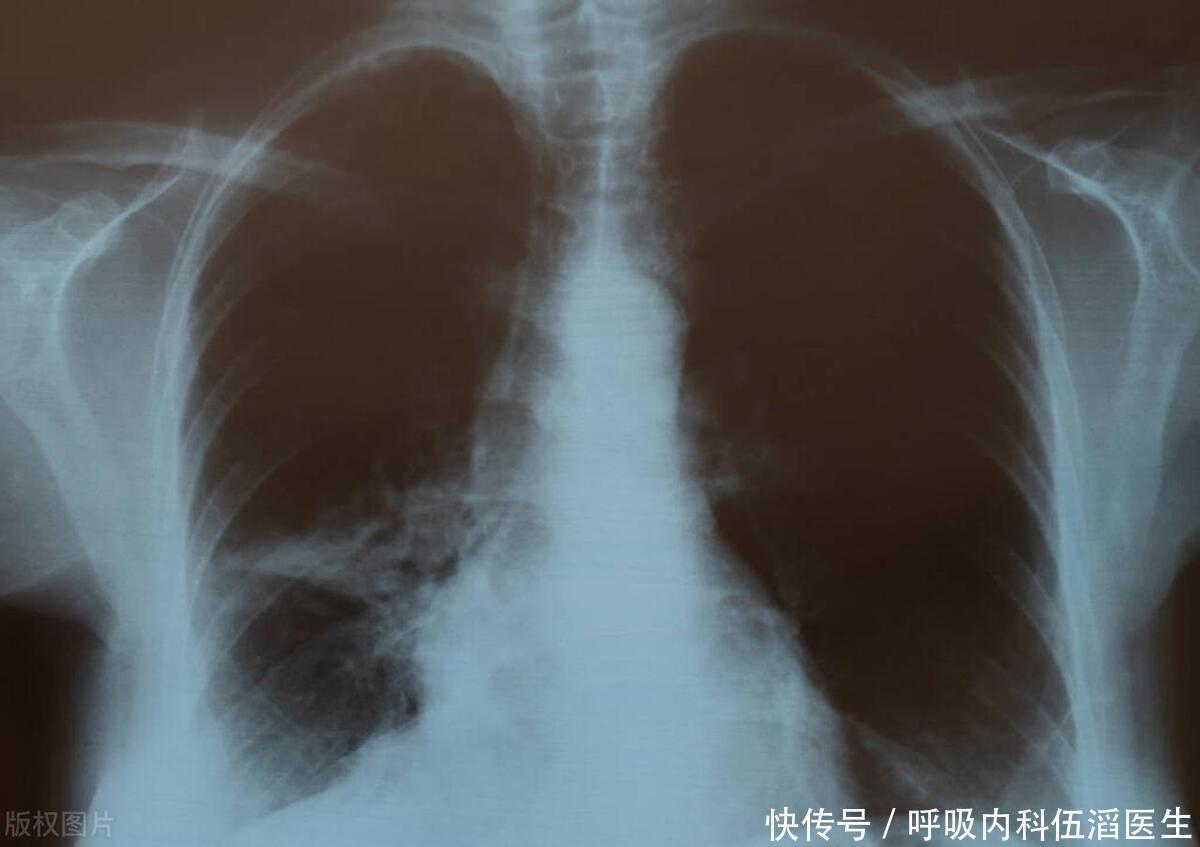

体内有“肺结节”的人,3 种“发物”要少碰,忍住不吃就很厉害了

肺结节

肺癌

肺腺癌